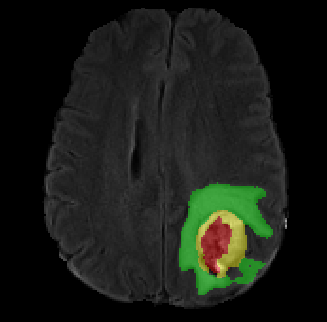

Data augmentation has been widely used for training deep learning systems for medical image segmentation and plays an important role in obtaining robust and transformation-invariant predictions. However, it has seldom been used at test time for segmentation and not been formulated in a consistent mathematical framework. In this paper, we first propose a theoretical formulation of test-time augmentation for deep learning in image recognition, where the prediction is obtained through estimating its expectation by Monte Carlo simulation with prior distributions of parameters in an image acquisition model that involves image transformations and noise. We then propose a novel uncertainty estimation method based on the formulated test-time augmentation. Experiments with segmentation of fetal brains and brain tumors from 2D and 3D Magnetic Resonance Images (MRI) showed that 1) our test-time augmentation outperforms a single-prediction baseline and dropout-based multiple predictions, and 2) it provides a better uncertainty estimation than calculating the model-based uncertainty alone and helps to reduce overconfident incorrect predictions.